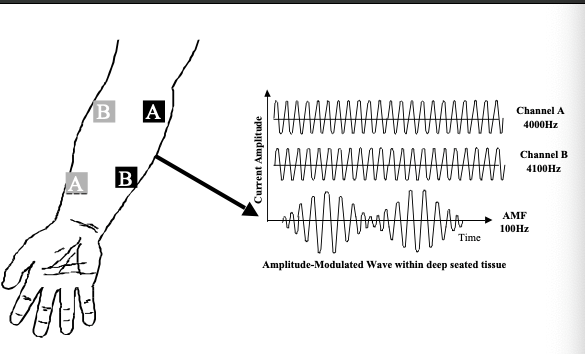

神经肌肉电刺激治疗上肢瘫痪

使用神经肌肉电刺激治疗上肢瘫痪作者:Mikayla Murphy Martin, R.、Johnston, K. 和 Sadowsky, C. (2012)。神经肌肉电刺激辅助抓握...